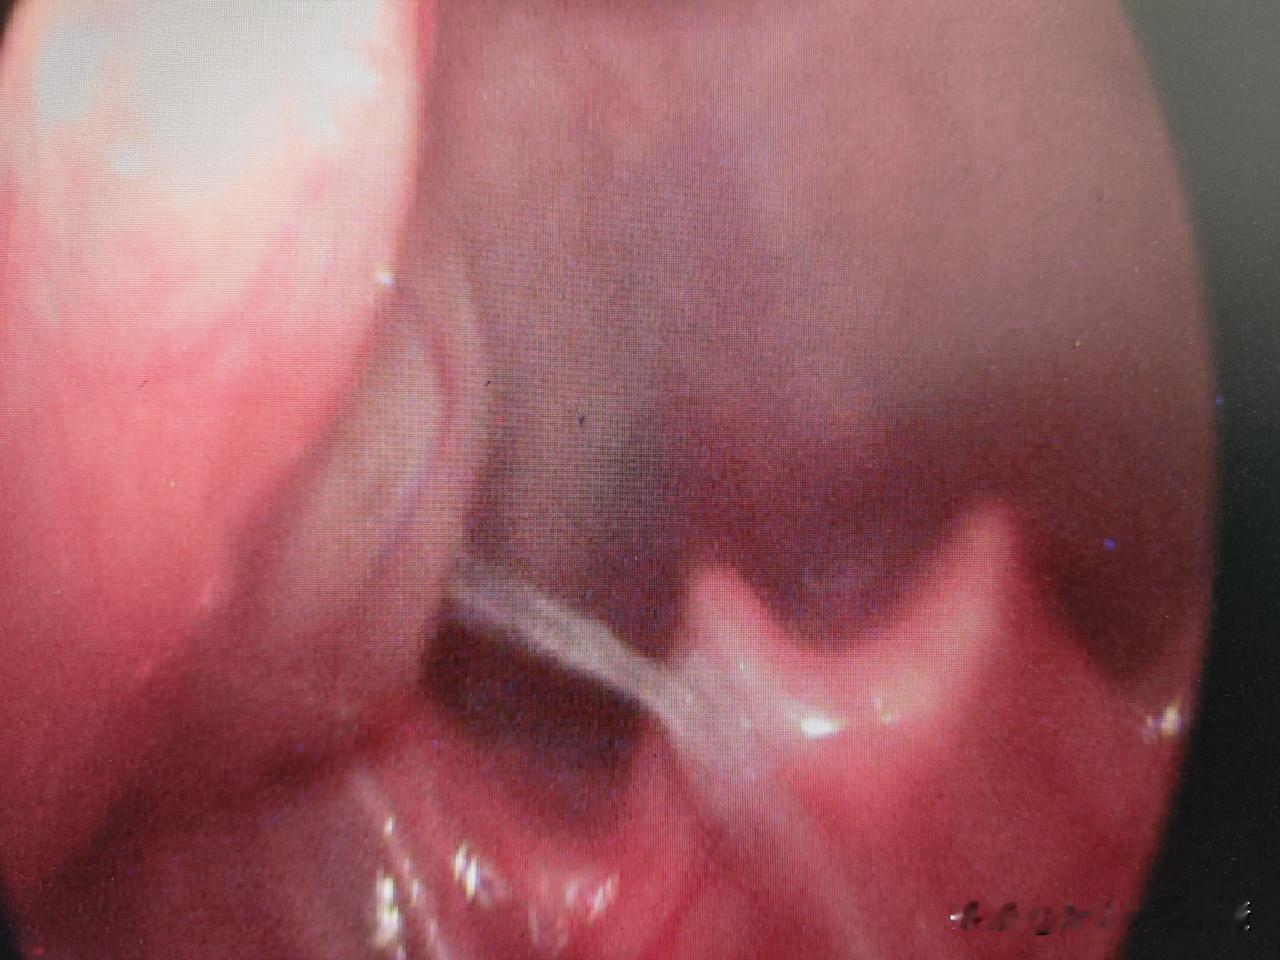

咽痛痰中带血丝今天门诊遇到一个18岁大一的男生,长得高高帅帅,患者的主诉就是右侧